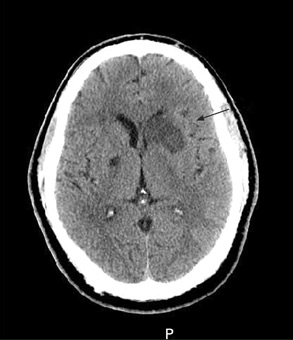

- TC de crânio sem contraste